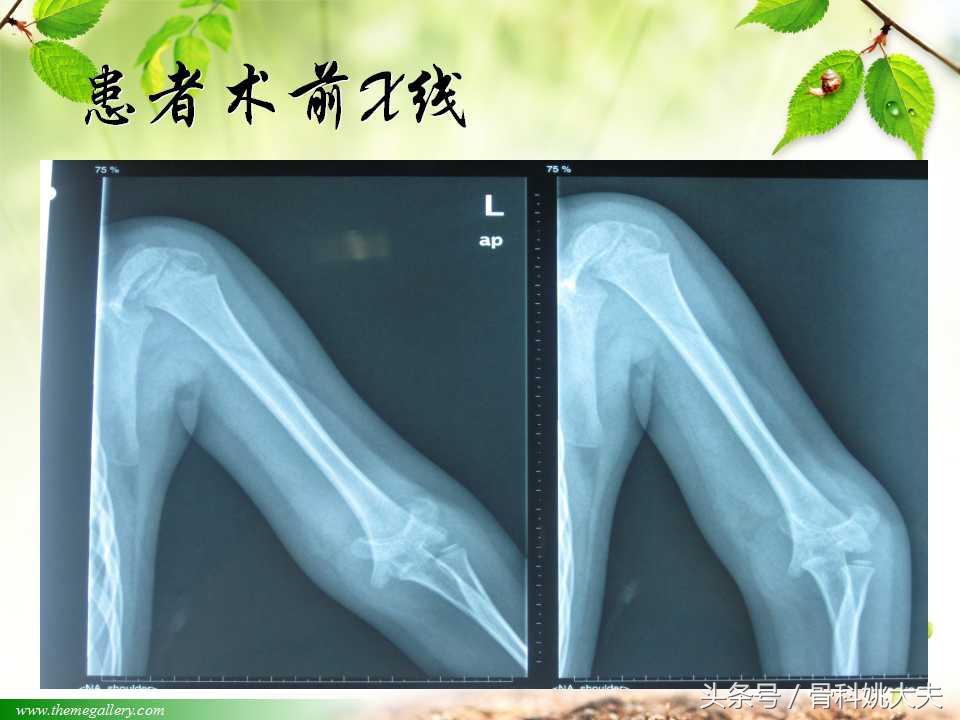

到底有什么办法治疗肱骨髁上骨折呢?今天带来相关教学课件。